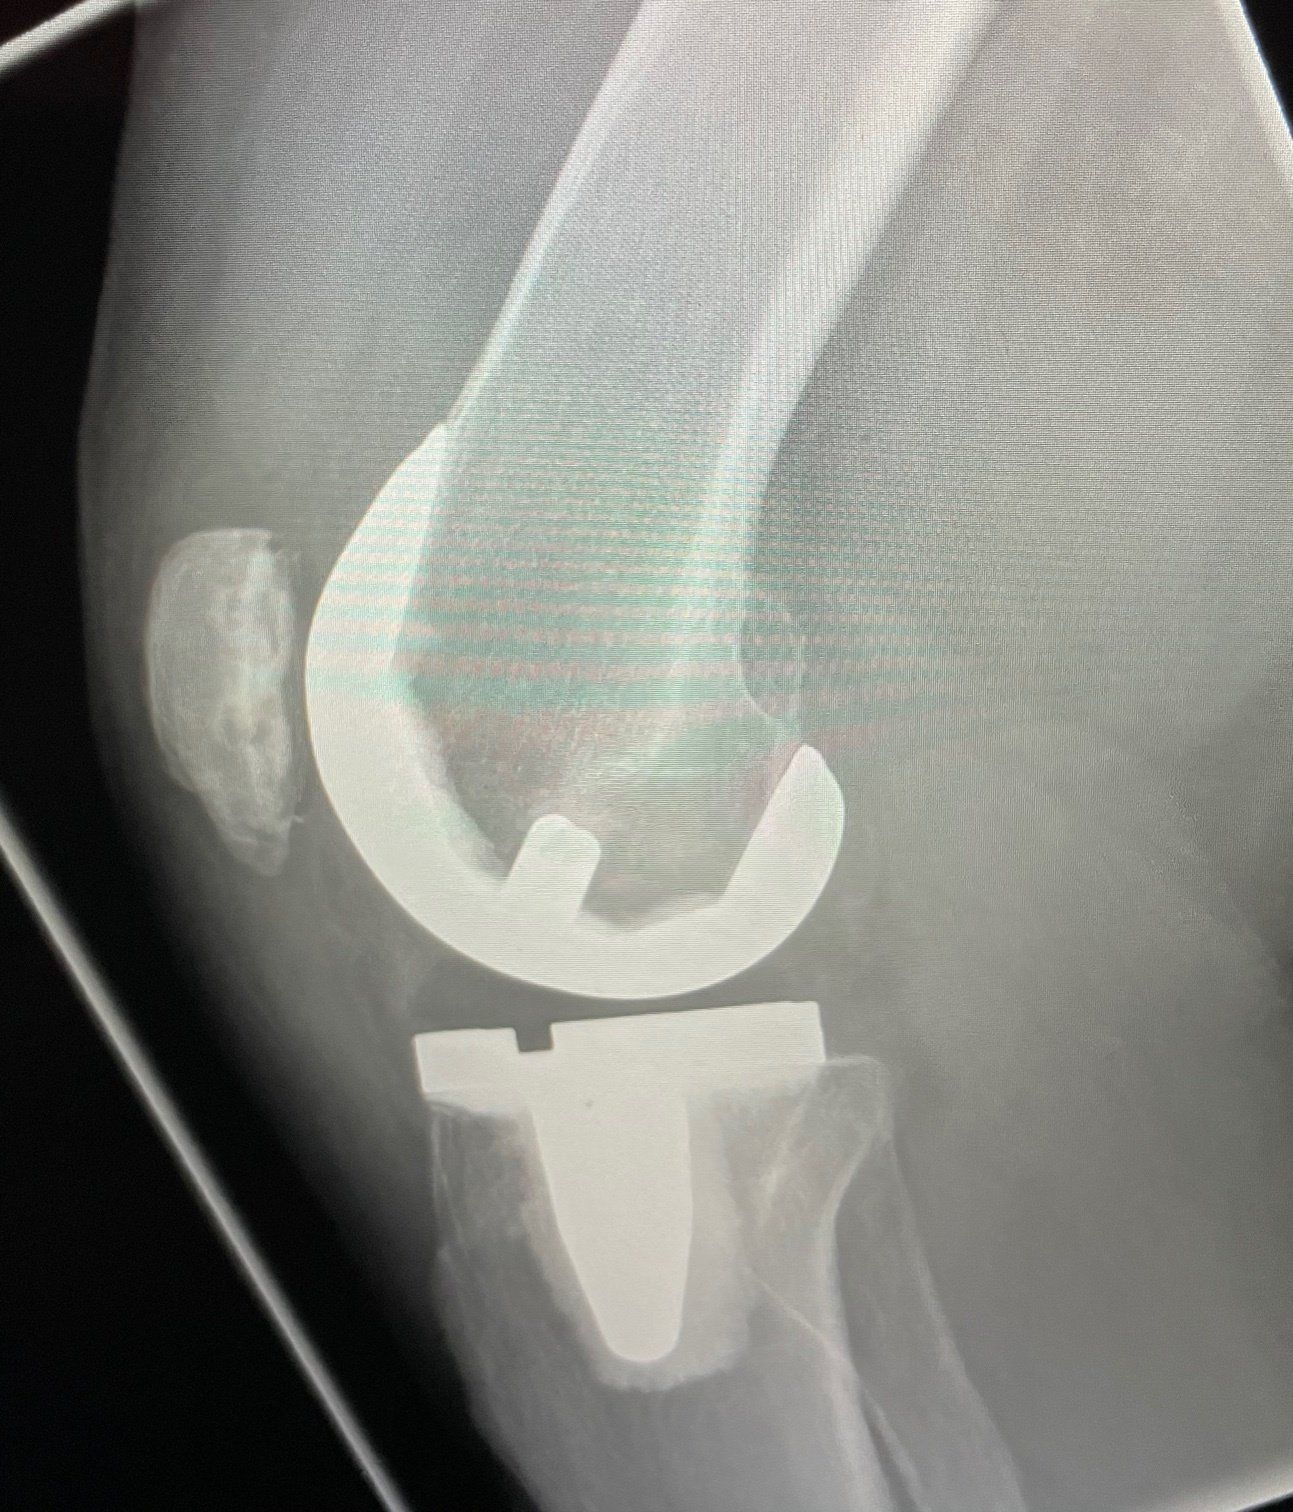

Cementless Knee Replacements

Mr Wall is now able to offer DePuy Attune Cementless total knee replacements through his private practice at Nuffield and Spire Hospital Leeds. This technique allows the latest generation of total knee replacements to undergo

complete bio-integration for optimal long-term results.